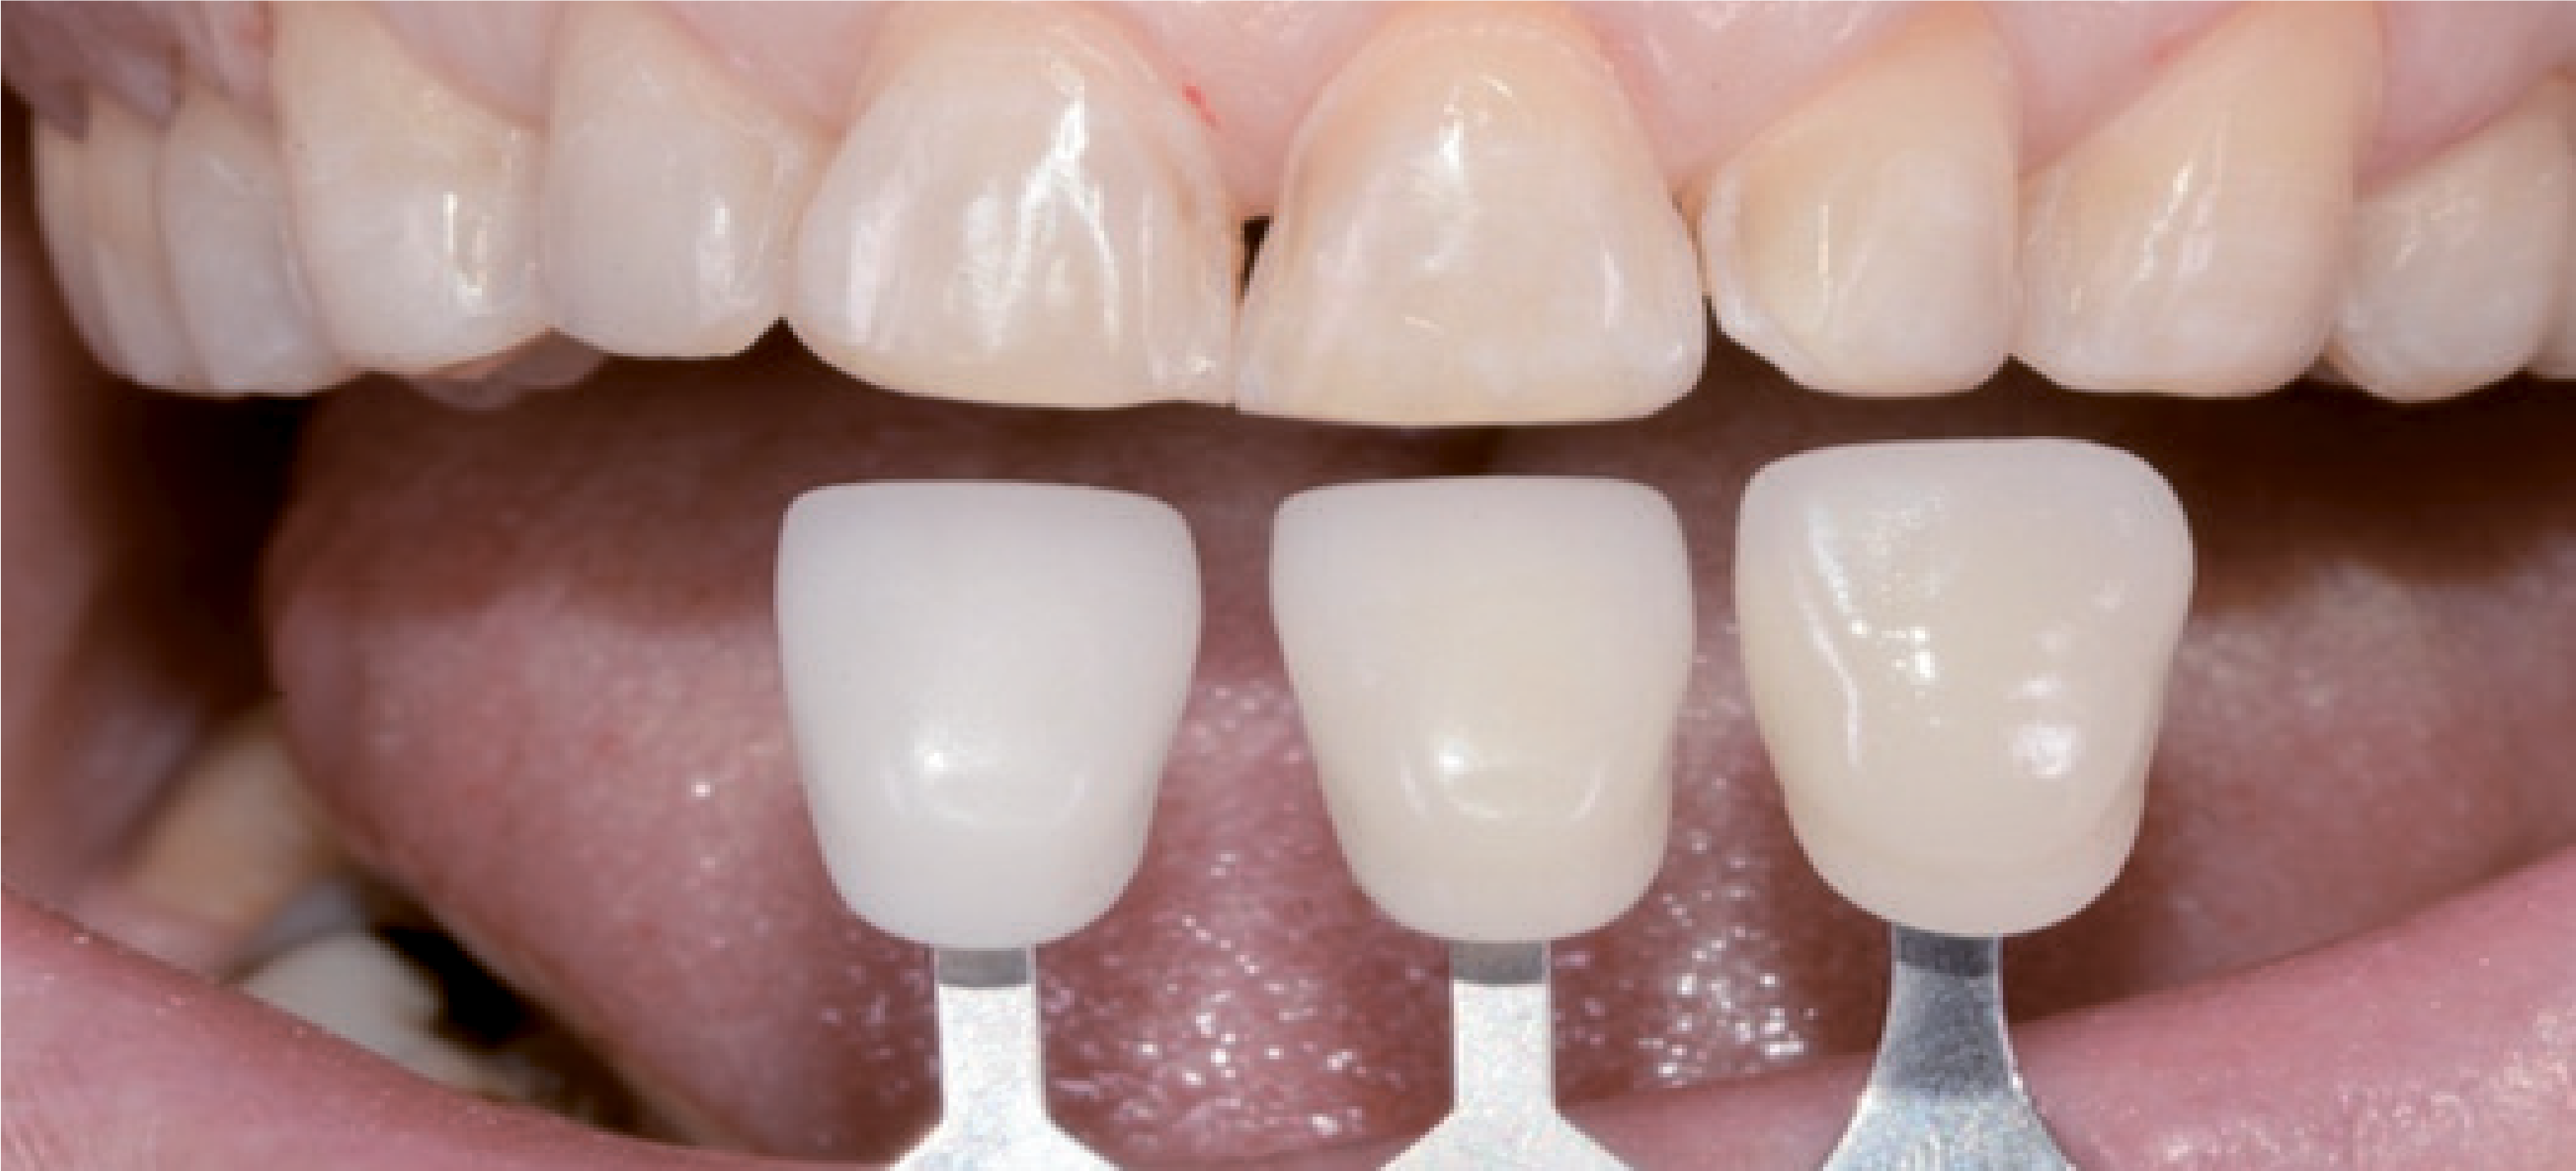

Відповідно, пришийкові кордони залишилися в емалі над поглибленнями. Тут основне завдання полягало в тому, щоб створити надійне з'єднання з емаллю. Шийкові відпрепаровані ділянки подовжили й вивели у міжзубні зони. Тут краям відпрепарованих ділянок надали невеликий скіс – на вестибулярному боці міжзубних точок контакту без ослаблення контакту проксимальної поверхні, щоб забезпечити стабільність і виключити будь-які зміщення. Поверхня відпрепарованих ділянок була згладжена полірувальним диском. Перед зняттям відбитка визначили відтінок зуба (мал. 13).

У стоматологічній лабораторії для зубів 15-25 були виготовлені пресовані вініри e-max, покриті полевошпатною порцеляною. Завдяки використанню техніки «spot etch» тимчасові реставрації вдалося легко видалити скалером. Відпрепаровану поверхню очистили матеріалом ConsepsisScrub (Ultradent). Для остаточного встановлення реставраційних конструкцій скористалися VitiqueCementationSystem (DMG). За допомогою пробних паст різних відтінків, аналогічних адгезивним цементам, за допомогою системи Vitique можна у всіх подробицях змоделювати остаточний результат. Оскільки порцелянові вініри тонкі та прозорі, цьому етапу приділили максимум уваги. Щоб приміряти реставраційні конструкції, використовували примірочні пасти, які містять гліцерин і є у комплекті VitiqueCementationKit (DMG). Вони дозволяють ідеально змоделювати остаточний результат (мал. 17).